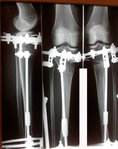

Пациентка - 37 лет.

Диагноз: варусная деформация голеней. Ротация с обеих сторон.

Дата операции - 24.10.2019г.